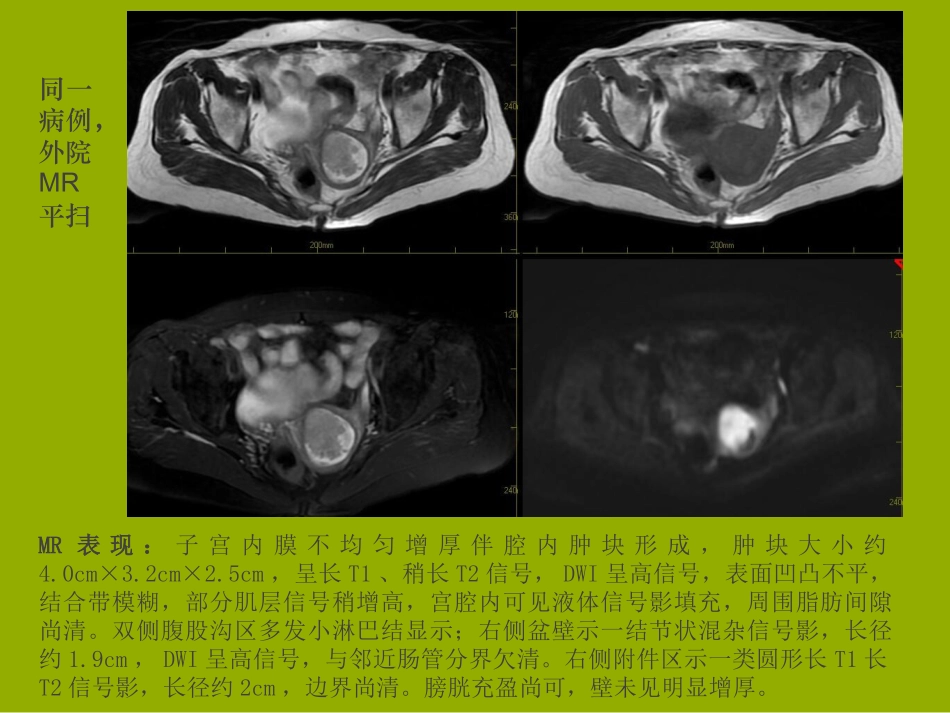

患者李某,女,69岁,下腹疼痛1月。科室影像讲座系列病例讨论之子宫内膜癌本院MR平扫+增强MR表现:子宫明显增大,宫腔积液、扩张,宫体后壁不规则增厚,边缘不规则呈菜花样突出,增强病灶可见强化。右侧附件区可见一结节影,大小约2.3cmx1.8cm,周围可见多发环状长T1长T2信号,IRFSE呈高信号。盆腔少量积液。MR印象:???MR表现:子宫内膜不均匀增厚伴腔内肿块形成,肿块大小约4.0cm×3.2cm×2.5cm,呈长T1、稍长T2信号,DWI呈高信号,表面凹凸不平,结合带模糊,部分肌层信号稍增高,宫腔内可见液体信号影填充,周围脂肪间隙尚清。双侧腹股沟区多发小淋巴结显示;右侧盆壁示一结节状混杂信号影,长径约1.9cm,DWI呈高信号,与邻近肠管分界欠清。右侧附件区示一类圆形长T1长T2信号影,长径约2cm,边界尚清。膀胱充盈尚可,壁未见明显增厚。同一病例,外院MR平扫MR印象:1.子宫内膜不均匀增厚伴腔内肿块和宫腔积液,考虑为恶性肿瘤性病变,肌层受侵可能。2.右侧盆壁结节状混杂信号影:附件病变、迂曲血管、或其他;另右侧附件区类圆形长T1长T2信号影,考虑为囊肿可能,其它待排。手术记录(部分):子宫稍萎缩,形态规则,色红润,右侧输卵稍增粗,右侧卵巢、左侧附件外观未见明显异常,盆腔淋巴结未见明显肿大,部分肠管、网膜与双侧附件膜性粘连。髂总、髂内外淋巴结及股深淋巴结及闭孔淋巴结清扫。取出双侧盆腔淋巴结。可吸收线连续缝合阴道残端。剖视子宫,子宫内膜广泛菜花样病灶,见部分肌层受侵,宫颈及颈管肉眼未见明显异常。病理诊断:(子宫)宫内膜低分化腺癌,结合形态学及免疫表型考虑透明细胞癌,浸及肌壁内1/2层,未累及宫颈管,慢性宫颈炎;(双宫旁、双侧附件)未见癌累及;(左盆腔淋巴结5枚,右盆腔淋巴结6枚)均未见癌转移(0/11)。免疫组化:CK7(+),Vim(+),ER(+),PR(-),CK5/6(-),P40(-),WT-1(-),NapsinA(-),P53(+),P16(-),CA125(+),Ki67(+,约50%)。临床分期:Ib期(2008FIGO分期)子宫内膜癌的MRI表现及分期杨贵磁共振成像是子宫病变首选的影像学检查方法之一,其最重要的作用在于肿瘤分期,对肿瘤的诊断和鉴别诊断,具有非常重要的临床意义。磁共振成像的优势妇产科MR检查注意事项病人检查前一定要特别了解:1、是否怀孕,月经状况、周期2、是否服用避孕药或其它激素类药物3、有无手术史或放疗病史4、是否带有节育环或其它金属植入物MR检查技术1、小FOV,薄层比较好;2、T2WI抑脂序列对观察子宫内膜及子宫肌瘤比较好,但常规T2WI不能少;3、DWI序列对观察盆腔淋巴结转移及骨骼转移效果好;4、增强扫描最好TIWI抑脂;5、中等量尿液。MR检查技术1、小FOV,薄层比较好;2、T2WI抑脂序列对观察子宫内膜及子宫肌瘤比较好,但常规T2WI不能少;3、DWI序列对观察盆腔淋巴结转移及骨骼转移效果好;4、增强扫描最好TIWI抑脂;5、中等量尿液。MR扫描定位子宫卵巢解剖结构子宫长约7-cm,宽4-5cm,厚2-3cm,呈前倾前屈位,屈—与宫颈呈170夹角,倾—宫体与阴道呈90度夹角。宫颈管成年长2.5--3.0cm,宫颈与宫体的比例因年龄而异,婴儿期为2:1,成年妇女为1:2,老人为1:1,宫颈管粘膜为柱状上皮,宫颈阴道部为磷状上皮,磷状上皮与柱状上皮交界处是宫颈癌的好发部位。成年妇女的卵巢大小为4cmx3cmx1cm,绝经后卵巢萎缩。妇女一生中有400-500个卵泡发育成熟并排卵。卵子排出后,卵泡转化为黄体。子宫卵巢磁共振成像宫体分三层信号:中心高信号代表内膜和分泌物中间薄的低信号带(结合带)为子宫肌内层周围呈中等信号代表子宫肌外层结肠子宫肌层子宫腔结合带膀胱子宫颈子宫直肠凹直肠阴道结合带膀胱基质直肠子宫肌子宫内膜宫颈内管宫颈子宫内膜随月经周期的变化而变化,随年龄变化而变化子宫内膜青春期开始受卵巢激素的影响,其表面2/3能发生周期性变化称为功能层,靠近子宫肌层的1/3内膜无周期性变化,称为基底层。卵泡期,月经第7天分泌期,月经第26天育龄期妇女绝经后妇女宫颈T1WI表现为均匀一致的稍低信号,由于宫颈粘液的缘故,可呈稍高信号。高分辨T2WI可看到5层结构最内层:高信号粘液粘膜层:高信号,低于粘液信号纤维基质:纤...